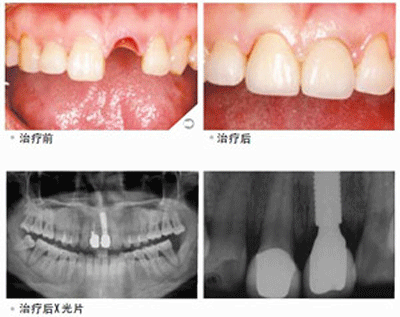

想要具体了解牙齿缺失福州哪家医院好 点击【在线咨询】直接问医生!方便!快捷!牙齿缺失在目前修复方式使种植牙,使用时间久,稳固耐用,而且舒适美观,而且还能即拔即中,即种即用。种植牙这样的特点大大的方便了人们的生活。但在医院选择方面却很为难,牙齿缺失福州哪家医院好?直接与医院在线医师一对一通话,方便!快捷!了解详情就医指导。

贝臣齿科率先引进微创术,国内医生级医生进行种植牙手术,利用手术方式来完成种植牙过程。与传统的种植牙相比,具有以下优势: